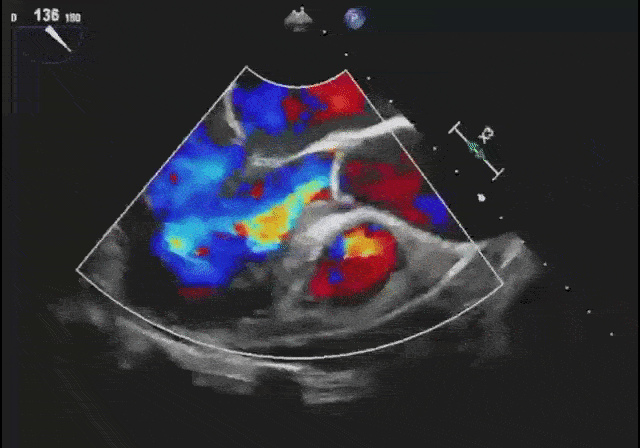

“二尖瓣夹合器位置稳定……彩色多普勒超声显示仅微量二尖瓣残余返流……主动脉瓣释放成功,未见明显反流,未见明显瓣周漏,患者生命体征平稳……”

心超:二尖瓣夹合满意,双孔形成,几乎无残余返流